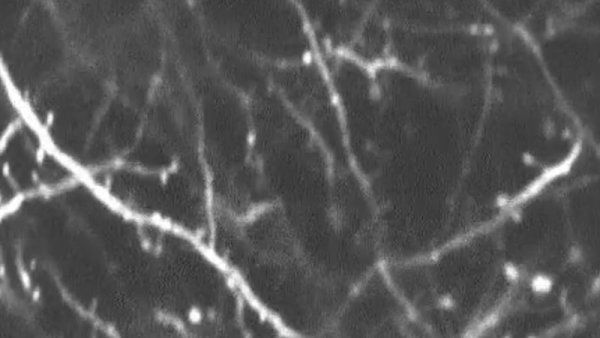

Image In the human brain, neurofilament light chain (NfL, shown in brown) is seen in brain cells and the neural wires that connect them. UCSF